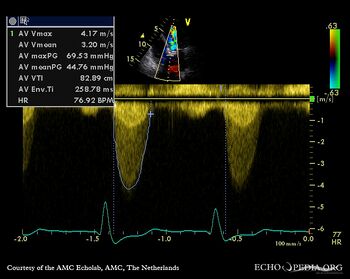

| Continuous-wave Doppler signal of transaortic flow | Pulsed-wave signal of flow in LVOT |